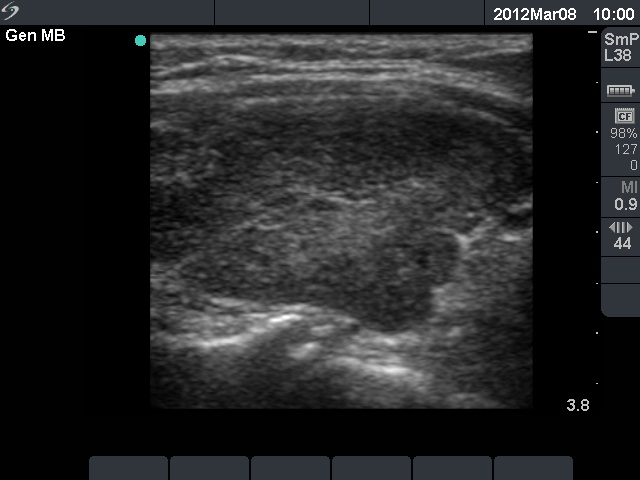

Follow-up examination 12 months later (second row):

Clinical presentation: The patient did not undergo radioiodine therapy. She was well and euthyroid on thyrostatic therapy in the previous year.

Palpation: Both thyroids were enlarged and moderately firm.

Result of blood test: subclinical hyperthyroidism on daily 10 mg methimazole (TSH undetectable, FT4 13.4 pM/L, FT3 5.05 pM/L).

Ultrasonography: The extent of hypoechogenic areas have decreased, otherwise the pattern was unchanged.We suggested again a repeat radioiodine therapy.